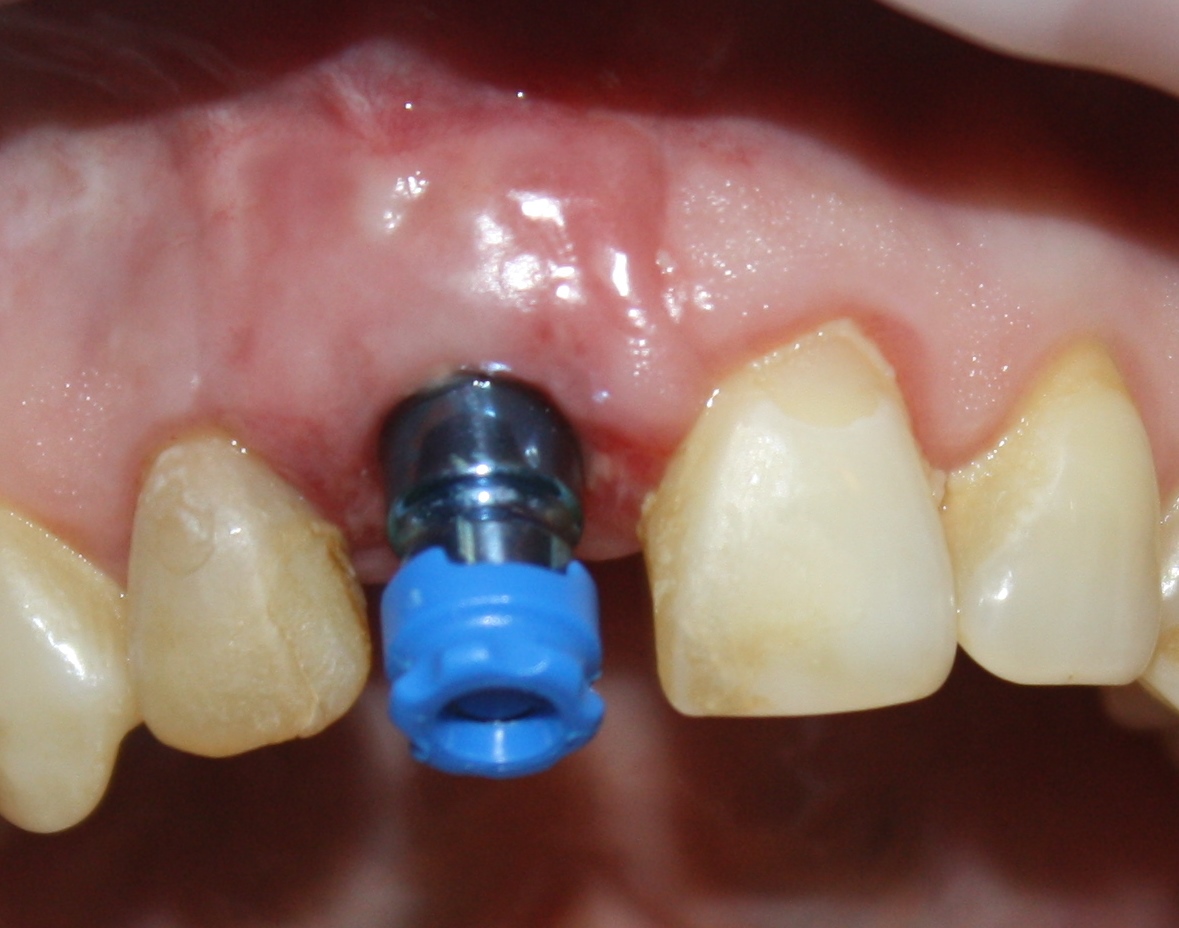

Немедленная имплантация — оптимальное решение в любой клинической ситуации